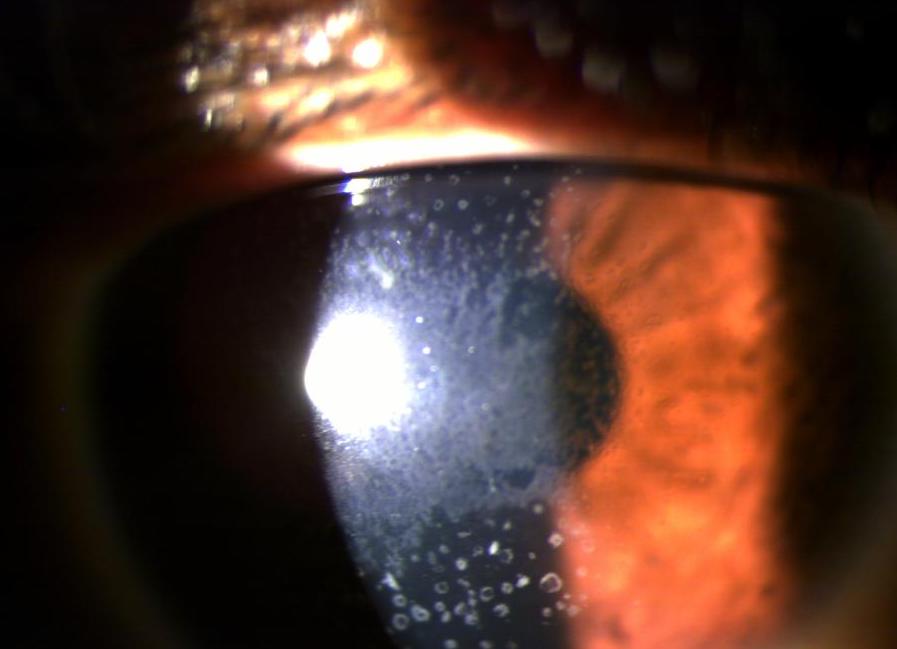

Case: Corneal erosions

A 27-year-old female attended your practice due to recurrent epithelial corneal erosions. The visual acuity in both eyes is 6/15 (0.4 in decimal scale). The patient has no history of ocular trauma and is in good general health. Furthermore, the patient has noticed blurry vision over the last 5-7 years and frequently changes her glasses. She has also had several treatments for epithelial erosions, which were thought to be due to rubbing her eyes after working on a computer extensively. It's important to note that the patient has astigmatism, but her current glasses do not provide adequate vision.